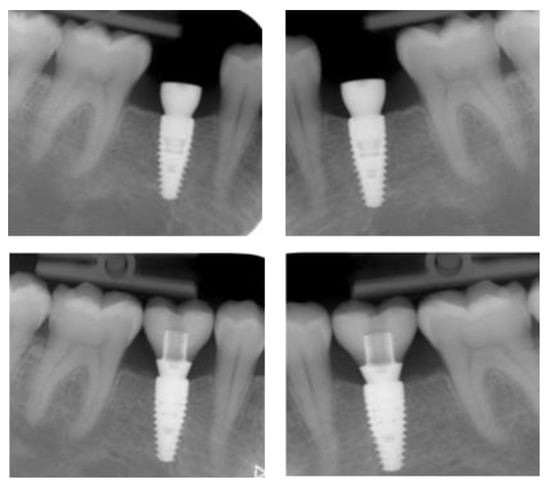

3.2. Marginal Bone Level Outcomes

| Mesial Marginal Bone Level (2D) [mm] after Immediate Placement | ||||||||

|---|---|---|---|---|---|---|---|---|

| Patient | 1 | 2 | 3 | 4 | 5 | Median | IQR | |

| Implant position | 45 | 35 | 45 | 45 | 13 | 23 | NA | NA |

| Post-OP mesial | 1.8 | 0.0 | 0.1 | 3.0 | 0.4 | 0.4 | 0.4 | 0.18–1.45 |

| 1 year mesial | 0.6 | 0.0 | 0.1 | 1.5 | 0.1 | 0.1 | 0.1 | 0.1–0.48 |

| Post-OP distal | 1.2 | 0.0 | 0.1 | 3.0 | 0.4 | 0.4 | 0.4 | 0.18–1.0 |

| 1 year distal | 0.6 | 0.0 | 0.1 | 1.5 | 0.2 | 0.0 | 0.2 | 0.03–0.5 |

| Marginal Bone Level (2D) [mm] after Delayed Placement | ||||||||

| Implant position | 35 | 45 | 35 | 35 | 35 | 45 | NA | NA |

| Post-OP mesial | 2.0 | 1.0 | 0.2 | 0.6 | 0.2 | 0.2 | 0.4 | 0.2–0.9 |

| 1 year mesial | 1.6 | 0.5 | 0.0 | 0.3 | 0.1 | 0.1 | 0.3 | 0.1–0.45 |

| Post-OP distal | 0.0 | 0.5 | 0.0 | 0.6 | 0.1 | 0.1 | 0.1 | 0.03–0.4 |

| 1 year distal | 0.0 | 0.2 | 0.0 | 0.3 | 0.1 | 0.1 | 0.1 | 0.03–0.18 |